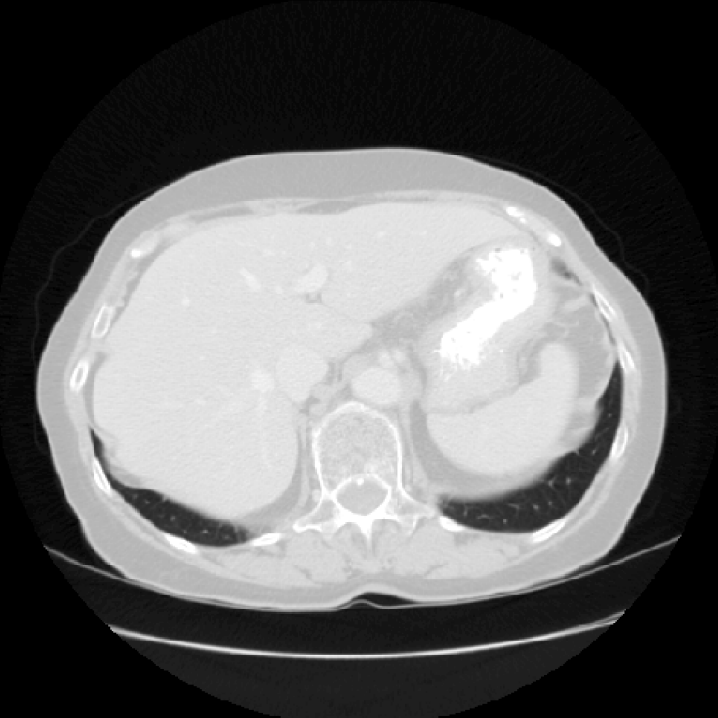

Slices Descriptions

(a) [Uncaptioned image] This image is a coronal CT scan of the chest, displaying the lungs, heart, and surrounding anatomical structures. The lungs appear as large, dark areas on either side of the image, with visible branching airways. The heart is centrally located, appearing as a lighter, more solid structure. The spine is visible in the background, running vertically along the center. The ribs are seen as curved, lighter lines on either side of the chest. There are also various soft tissues and blood vessels visible. The scan provides detailed cross-sectional imaging, useful for diagnosing and evaluating thoracic conditions.

(b) [Uncaptioned image] This image is a coronal MRI scan of the brain, providing a crosssectional view of the cerebral structures. The scan clearly shows the symmetrical arrangement of the brain’s hemispheres, with the central sulcus and other gyri and sulci visible on the surface. The ventricular system is also apparent, with the lateral ventricles appearing as dark, butterfly-shaped structures in the middle. The surrounding gray matter and white matter can be distinguished by their varying shades of gray. This type of imaging is crucial for diagnosing and evaluating neurological conditions, as it highlights differences in tissue density and structure within the brain.

(c) [Uncaptioned image] This image is a sagittal MRI scan of the thoracic region, prominently displaying the heart and surrounding structures. The heart is centrally located, with its chambers and major blood vessels visible, including the aorta. The lungs, with their branching bronchial structures, can be seen around the heart. The vertebral column runs vertically along the left side of the image, providing structural support and orientation. The grayscale contrast highlights different tissue densities, aiding in distinguishing between various anatomical features. This detailed imaging is crucial for diagnosing cardiovascular and thoracic conditions.

(d) [Uncaptioned image] This image is a transverse CT scan of the abdomen, offering a detailed cross-sectional view of the internal organs. The large, rounded structure in the center is likely the liver, with its distinct texture and density. Adjacent to it, the stomach and spleen are visible, with the spleen showing a brighter area indicative of different tissue or a lesion. The vertebral column is centrally located at the bottom, providing a structural reference. The grayscale contrast differentiates between various tissue densities, essential for identifying abnormalities. This detailed imaging is crucial for diagnosing abdominal conditions and guiding further medical evaluation and treatment.

(e) [Uncaptioned image] This image is a sagittal MRI scan of the abdomen, showcasing various internal structures in detail. Central to the image is a large, circular organ, likely the liver, with its characteristic texture and surrounding tissues. The diaphragm is visible, delineating the boundary between the thoracic and abdominal cavities. The vertebral column is seen running vertically along the left side, providing a reference point for orientation. The grayscale contrast highlights different tissue densities, facilitating the diagnosis and evaluation of abdominal conditions.